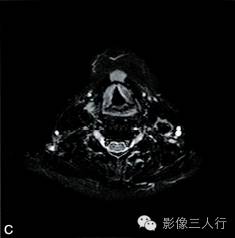

A~B. T1WI横断位;C~D. T2WI压脂横断位; E~F. T1WI压脂增强横断位;G. HE×100

卵圆形结节影位于舌骨中线,T1WI呈低信号,T2WI压脂序列呈稍高信号,信号均匀。增强后明显均匀强化,约1.3cm×0.8cm×1.6cm,其右前方下颌间隙内亦见一小结节,约0.7cm×0.4cm×0.5cm,信号特点与舌骨中线结节大致相同。颈部软组织结构清楚,未见异常信号影,气管居中,无受压或移位。颈部MRI平扫两侧见正常甲状腺组织,信号欠均匀(图A~F)。